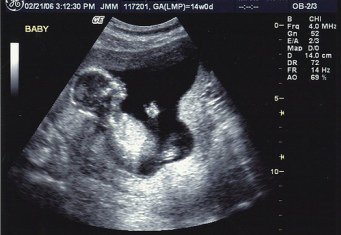

УЗИ на 17-й неделе беременности

Плод на этом сроке весит около 200 г и имеет в длину примерно 10-14 см. Кожа малыша все еще тонкая, но уже начинает формироваться прослойка жира. Движения малыша все активнее и сложнее, он уже может находить и сосать свой палец, малыш потягивается, чешется, шевелит ножками.